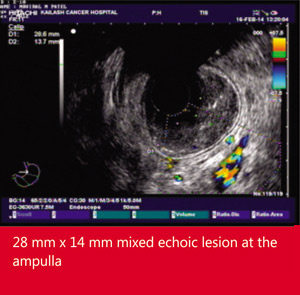

Case referred for evaluation of pancreatitis in a young non alcoholic male with normal spiral CT scan abdomen and MRCP He had 5-6 admissions for pain in abdomen with gastroenterologist of surat.

His EUS was done at Muni Seva Ashram, Goraj

EUS FNA and biopsy were Tubulovillous adenoma. Patient underwent surgical ampulloplasty and recovered well.